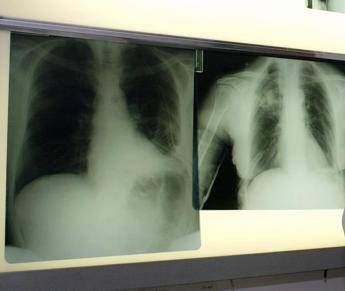

(Adnkronos) – BeOne Medicines, azienda oncologica globale, ha annunciato oggi che la Commissione europea ha approvato tislelizumab in combinazione con chemioterapia a base di etoposide e platino come trattamento di prima linea dei pazienti adulti con tumore del polmone a piccole cellule di stadio esteso (Es-Sclc). "Il tumore del polmone a piccole cellule in stadio esteso è notoriamente difficile da trattare per la sua natura aggressiva e necessita di nuove opzioni terapeutiche – afferma Silvia Novello, presidente di Women against Lung Cancer in Europe (Walce), direttore Oncologia medica all'Ospedale San Luigi Gonzaga di Orbassano e professore ordinario di Oncologia medica all'UniversitĂ degli Studi di Torino – I risultati dello studio Rationale-312 mostrano che tislelizumab piĂą chemioterapia ha migliorato la sopravvivenza rispetto al trattamento con placebo piĂą chemioterapia, evidenziando la capacitĂ di offrire migliori risultati per i pazienti eleggibili". L'approvazione nel tumore del polmone a piccole cellule di stadio esteso (Es-Sclc) – riporta una nota – si basa sui risultati di Rationale-312 (NCT04005716), uno studio multicentrico di fase 3 randomizzato, in doppio cieco, controllato con placebo, mirato a valutare l'efficacia e la sicurezza di tislelizumab in combinazione con platino (cisplatino o carboplatino a scelta dell’investigatore) piĂą etoposide, come trattamento di prima linea dei pazienti adulti con Es-Sclc. Lo studio, che ha randomizzato 457 pazienti, ha raggiunto l'endpoint primario, mostrando un miglioramento statisticamente significativo e clinicamente rilevante della sopravvivenza globale (Os) con tislelizumab in combinazione con chemioterapia, rispetto a placebo piĂą chemioterapia nella popolazione intent-to-treat (Itt). Come riportato sul 'Journal of Thoracic Oncology', all'analisi finale prevista dal protocollo la sopravvivenza mediana è risultata di 15,5 mesi per tislelizumab con chemioterapia rispetto a 13,5 mesi per placebo piĂą chemioterapia, con una riduzione del 25% del rischio di morte. Tislelizumab piĂą chemioterapia è stato generalmente ben tollerato e non sono stati identificati nuovi segnali di sicurezza. "In meno di 2 anni, tislelizumab è stato approvato in 4 patologie distinte nell'Ue, sottolineando la sua capacitĂ di produrre miglioramenti della sopravvivenza clinicamente significativi e un profilo di sicurezza ben caratterizzato in vari tipi di tumori – dichiara Mark Lanasa, Chief Medical Officer, Solid Tumors in BeOne Medicines – La nostra comprovata esperienza con le registrazioni di tislelizumab in 45 Paesi rafforza il nostro impegno a offrire trattamenti innovativi al maggior numero possibile di persone affette da cancro".  L'approvazione – prosegue la nota – si basa anche sui dati di sicurezza aggregati provenienti da piĂą di 3.900 pazienti trattati con tislelizumab sia in monoterapia (n=1.952) che in combinazione con chemioterapia (n=1.950) al regime di dosaggio approvato. Le reazioni avverse piĂą comuni di grado 3 o 4 (≥ 2%) con tislelizumab in combinazione con chemioterapia sono state neutropenia, anemia, trombocitopenia, iponatriemia, ipocalcemia, fatigue, polmonite, linfopenia, eruzione cutanea, diminuzione dell’appetito, aumento di aspartato aminotransferasi, e aumento di alanina aminotransferasi. Oltre al tumore del polmone a piccole cellule di stadio esteso, tislelizumab è approvato nell'Ue per 3 indicazioni nel tumore del polmone non a piccole cellule (Nsclc) nei setting di prima e seconda linea, come trattamento di prima linea dei pazienti eleggibili con carcinoma esofageo a cellule squamose non resecabile (Escc), nell'adenocarcinoma gastrico o della giunzione gastroesofagea (G/Gej) in combinazione con chemioterapia, e come trattamento di seconda linea nel carcinoma esofageo a cellule squamose localmente avanzato o metastatico, non resecabile dopo una precedente chemioterapia a base di platino. —salutewebinfo@adnkronos.com (Web Info)